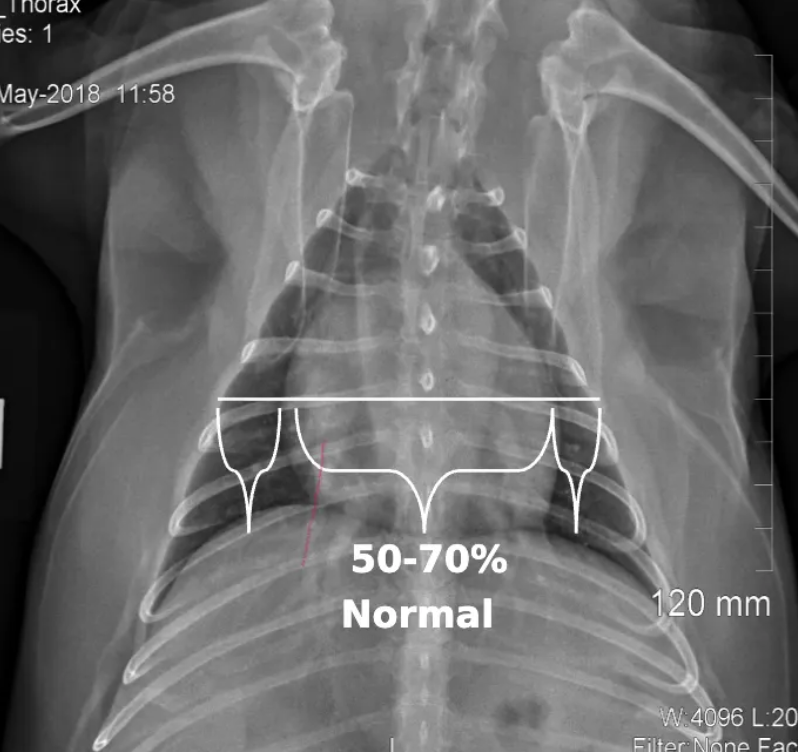

general cardiac width by cardiothoracic ratio in VD/DV view?

20